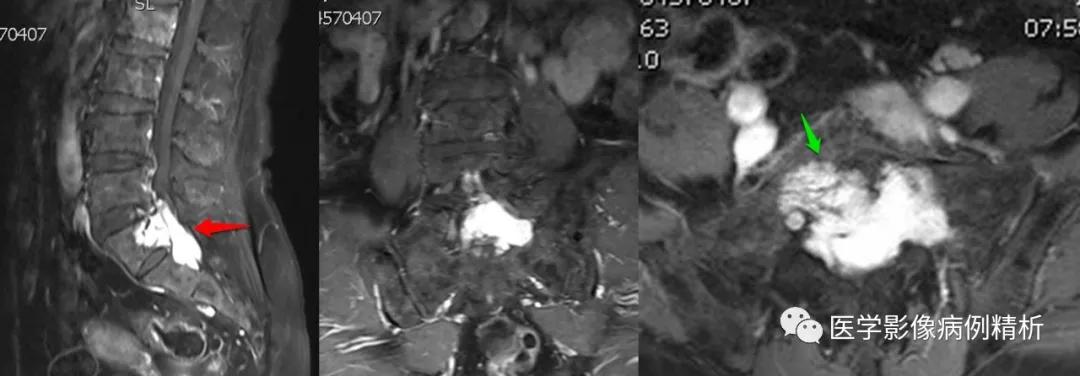

如图所示,分别为T1WI增强矢状位、冠状位、轴位,T1WI增强矢状位与T2WI压脂像非常相像,注意椎管内脑脊液信号,T1WI增强为低信号与T2WI压脂像高信号正好相反。红色箭头所示病灶明显强化,呈亮灯征感觉,清晰显示病灶范围,绿色箭头所示为病灶侵及骶1椎体后缘形成不规则形骨质破坏区。

红色箭头:病灶位于骶1-2椎体水平,轴位呈哑铃型,CT见骶1-2椎体后缘受侵、骨质破坏;MRI见病灶主体沿骶管及双侧骶孔生长,以左侧骶孔为著,T1低信号,T2稍高信号,压脂像高信号,接近脑脊液信号。

绿色箭头:骶1-2椎体后缘见信号向内部侵犯,边缘毛糙。